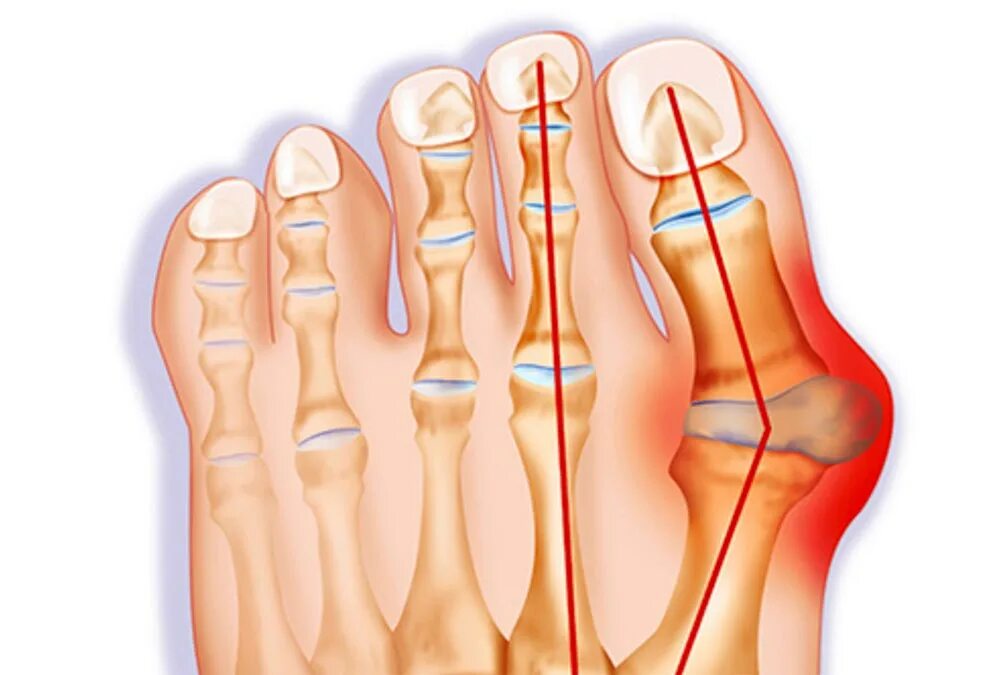

Подагра суставов стопы